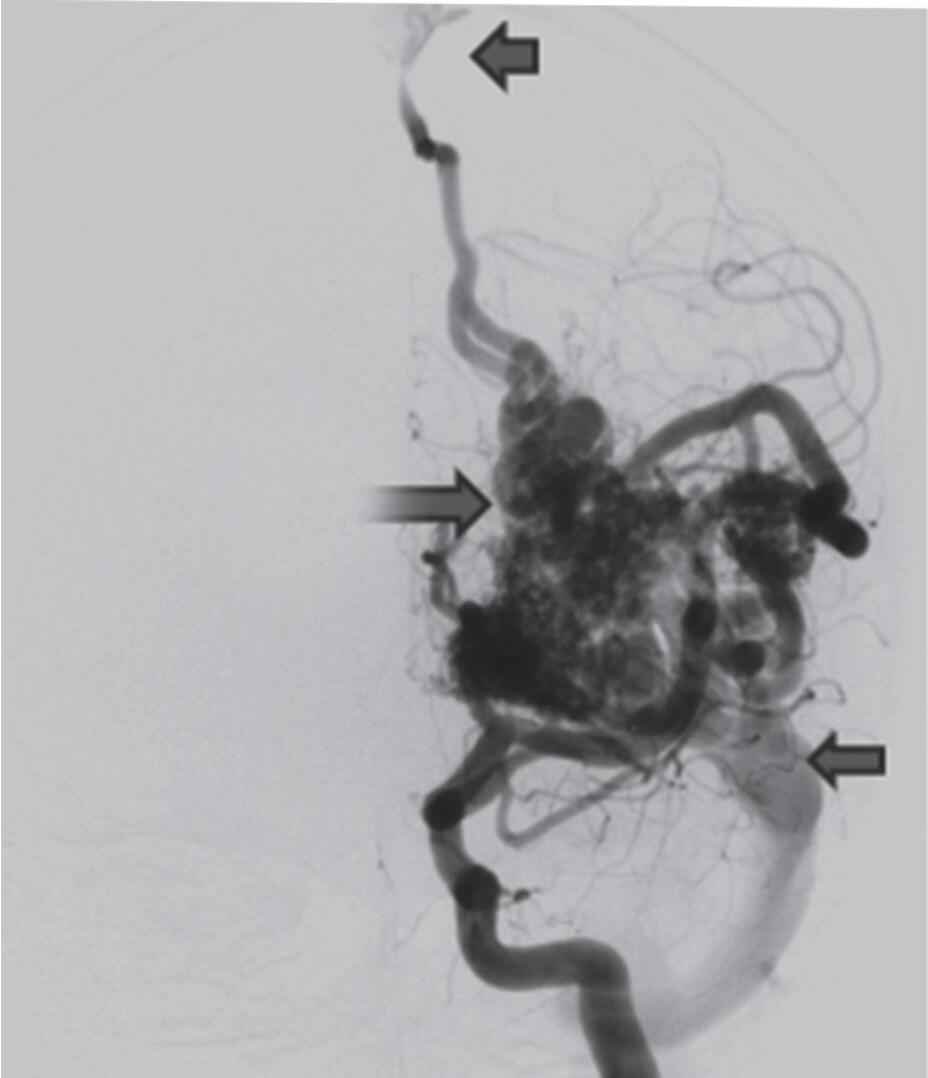

Fig. 1-8. (a-c) RNM T1 com contraste, cortes sagital (a), coronal (b) e axial (c) demonstrando MAV não rota com nidus localizado no lobo occipital à esquerda (setas longas). (d) Arteriografia digital cerebral com injeção de contraste via carótida direita (AP) mostrando a contribuição da carótida direita na irrigação da MAV contralateral. (e,f) Com injeção de contraste via carótida esquerda, em Perfil e AP respectivamente, observa-se nidus compacto nutrido por ramos da artéria cerebral média à esquerda e a veia de drenagem precoce se dirigindo para o seio sagital superior. Projeções em AP (g) e em perfil (h) demonstrando a contribuição do sistema vertebrobasilar por meio de ramos distais da artéria cerebral posterior à esquerda e drenagem para os seios sagital superior e sigmoide à esquerda (setas curtas).